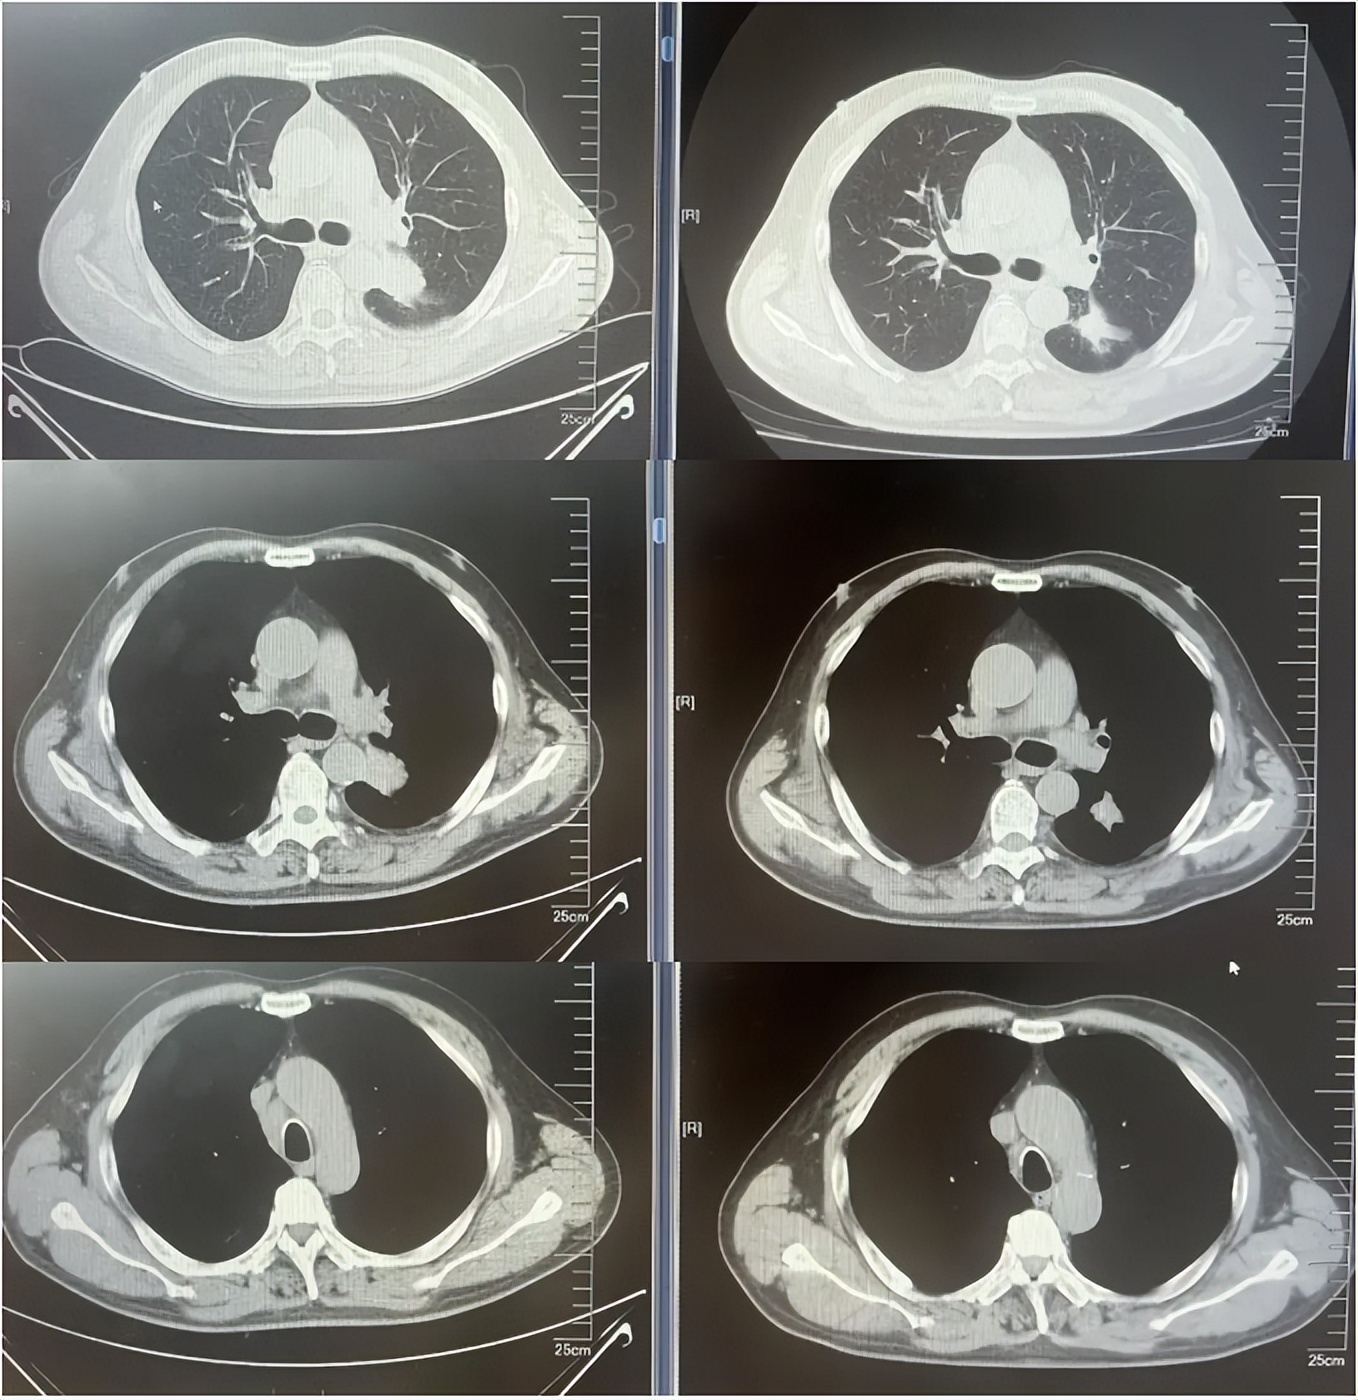

病例1:患者男,68岁。2024年6月以“胸闷气短1个月”为主诉于当地医院检查治疗。查CT提示左肺下叶肿物,纵隔、双肺门多发肿大淋巴结,左侧胸腔积液,左侧胸膜增厚。于当地医院行胸水穿刺引流查癌细胞提示肺腺癌。临床分期:cT2aN3M1a IVA期。患者于当地医院行血液基因检测未见敏感突变,使用AP方案化疗后病情进展。2025-1入我院后行肺穿刺活检,病例提示腺癌。行基因检测提示:ERBB2突变(丰度3.5%)。行德曲妥珠单抗(T-DXd)治疗至今。最佳疗效PR,目前持续有效中,PFS已超过7个月。患者使用德曲妥珠单抗期间出现II级恶心呕吐,经对症治疗可缓解。

德曲妥珠单抗治疗4周期(2025.5)疗效对比

德曲妥珠单抗治疗6周期(2025.7)疗效对比

病例1治疗经过

病例2:患者男,61岁。2023年8月于外院行肺CT提示:右肺下叶肿块。2023年10月23日于我院行单孔胸腔镜下右肺下叶切除术、肺门纵隔淋巴结扩清术。术后病理:腺癌低分化(腺泡型占30%,乳头型占30%,筛状占30%,微乳头占10%)。分期pT4N0M0 IIIA期。术后行基因检测提示HER2+(14%),PD-L1 2%+。术后行AC方案化疗4周期后行阿替利珠单抗维持治疗1年。末次用药时间:2024年11月1日。2025年2月复查肿瘤标志物升高,肺HRCT示:双肺多发结节,考虑转移。行血液基因检测提示:ERBB2 35.5%突变,CDK1 9.5%突变,MDM2 4.92%突变。患者DFS 14m,阿替利珠单抗停药后3个月出现复发转移,可见传统免疫治疗效果不佳。恰逢德曲妥珠单抗一线新尝试DESTINY-lung 04研究公布了入组标准和治疗方案,且该患在术后的组织基因检测和复发后的血液基因检测中都明确存在HER2突变,故行德曲妥珠单抗一线治疗。最佳疗效PR,目前治疗持续有效,PFS超过6个月。无药物相关不良反应发生。

德曲妥珠单抗治疗4周期(2025.4)疗效对比

病例2治疗经过